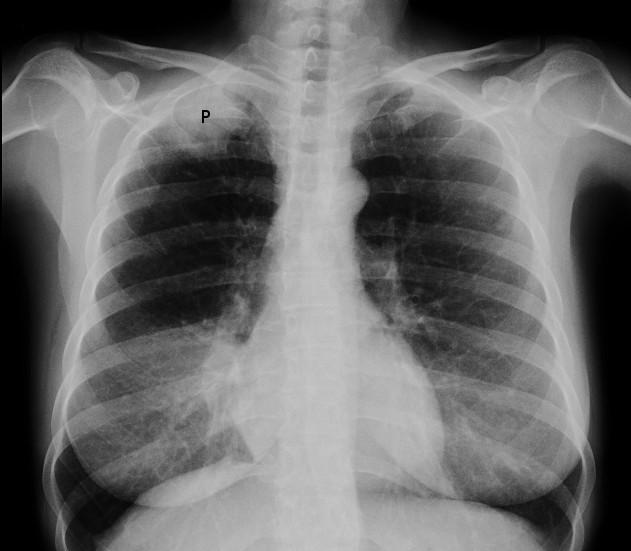

Radiografía de un tumor de Pancoast

Por Jmarchn, CC BY-SA 3.0vía Wikimedia Commons